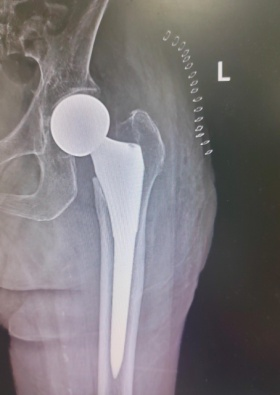

8月15日,由關節外科、運動醫學(xué)科主任餘金勝主刀,帶領手術團隊成(chéng)功進(jìn)行左側人工股骨頭置換術,術中用時(shí)不到30分鍾成(chéng)功置入髋關節假體,整個手術用時(shí)約80分鍾,術中仔細止血,術中無需輸血。

術後(hòu)醫護一體化查房,潘奶奶恢複非常好(hǎo),并于術後(hòu)3天下地,家屬高興極了,并表示幸虧做了這(zhè)個手術,讓老人家少遭罪。